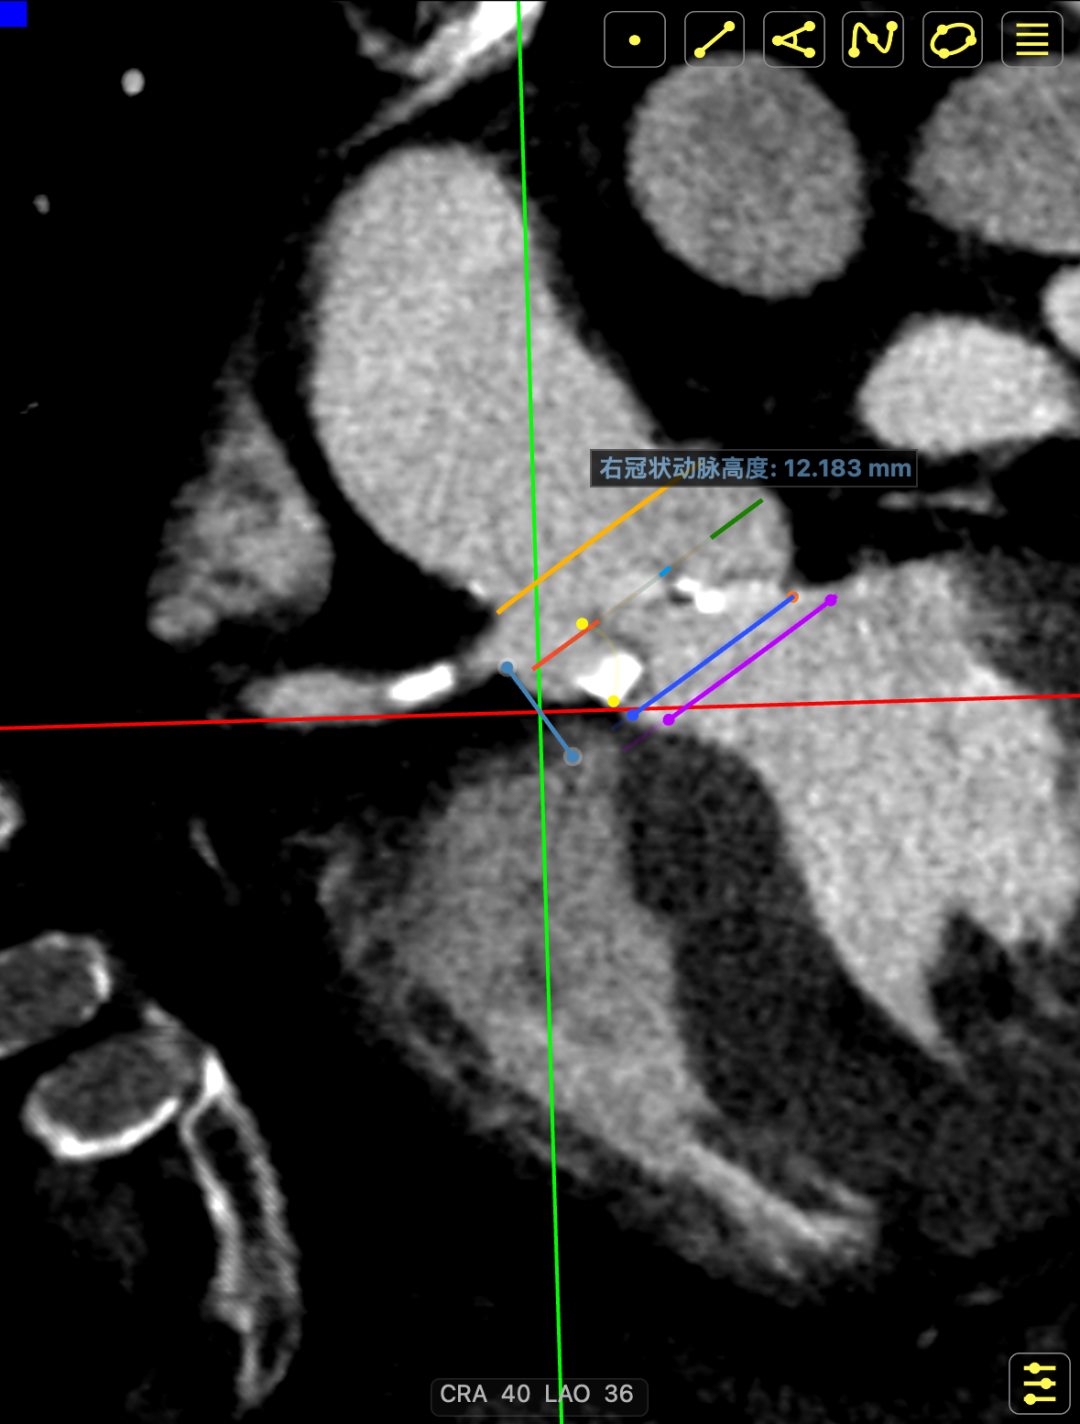

主动脉瓣多发钙化,主动脉瓣为type0型二叶瓣中重度钙化。主动脉瓣环面积折算直径约24mm。患者双侧冠脉开口高度可(左冠14.46mm,右冠18.29mm),主动脉升弓降部管壁不规则并钙化斑块影,主动脉弓并龛影。升主动脉管径36mm,降主动脉管径22mm。腹主动脉、双侧髂动脉管壁不规则并可见钙化斑块影,双侧髂总动脉及其分支髂内动脉管腔轻度狭窄。

主动脉升弓降部管不规则增厚并多发钙化,主动脉弓部左锁骨下动脉开口以远瘤样扩张,管径46*43mm。患者主动脉瓣环面积折算直径约26mm。升主动脉管径约32.5mm,降主动脉管径27.5mm;双侧冠脉开口高度可(左冠17.63mm,右冠12.18mm)。头臂血管右侧无名动脉、左侧颈总动脉、左侧锁骨下动脉管壁不规则增厚;头臂干起始部管壁钙化,管腔轻微狭窄。腹主动脉、双侧髂总动脉及其分髂内、髂外动脉管壁不规则增厚并钙化。